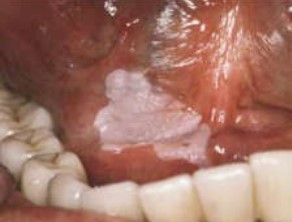

На снимке представлен(а) :

Варианты ответов

- Эритроплакия

- Бляшечная форма веррукозной лейкоплакии

- Экссудативно-гиперемическая форма красного плоского лишая

- Острый псевдомембранозный кандидоз